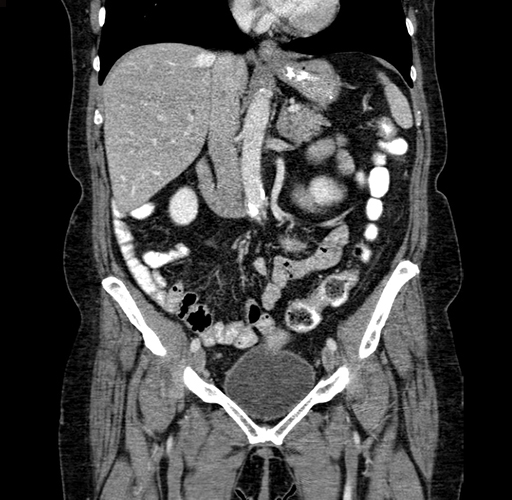

Pre-Chemo: Axial Venous

Pre-Chemo: Coronal Venous